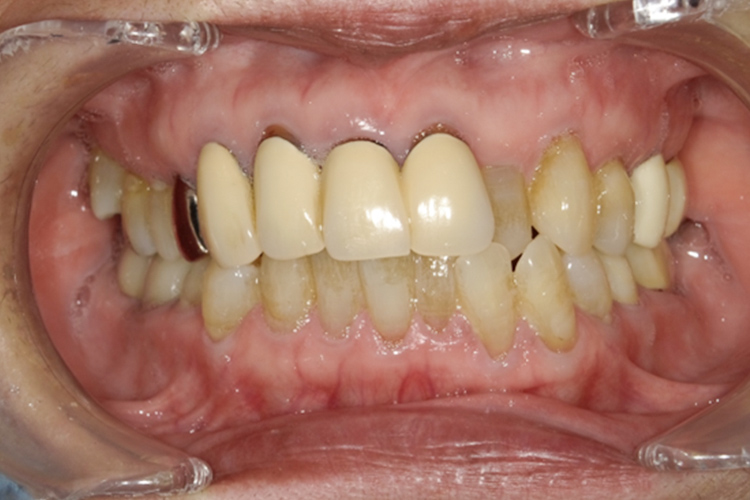

治療前

治療後